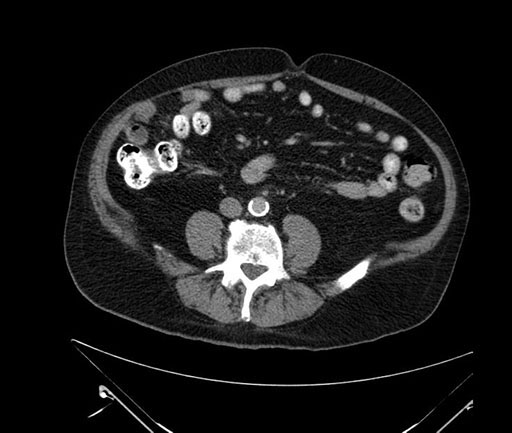

Axial - stented